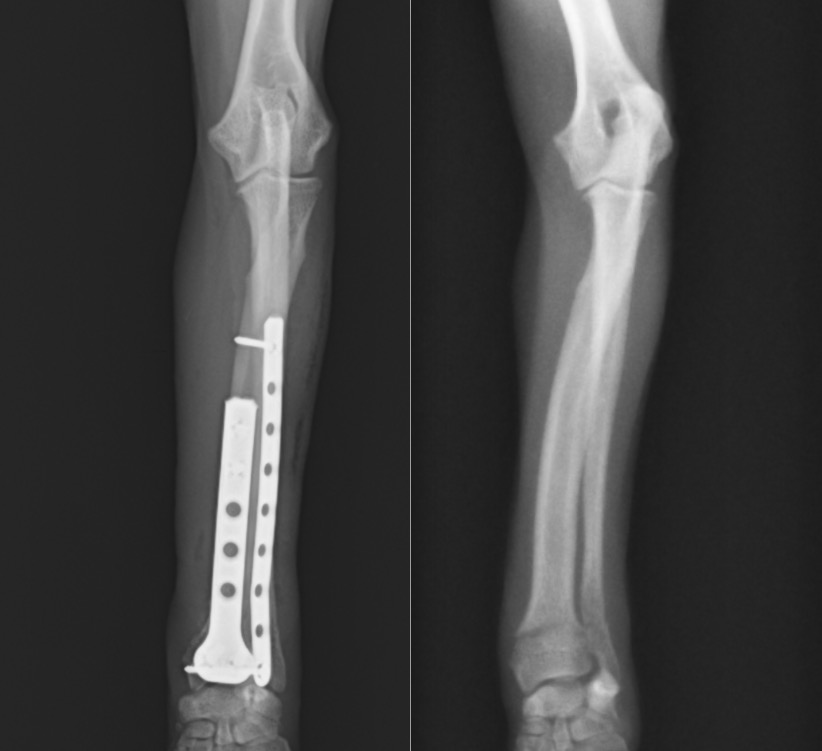

手術はダブルプレート法で行いました。

正面に1.5㎜コンディラープレート、側面に1.1mmストレートプレートを設置し、

結果的には手首の関節に近い小さい骨片にも3本のスクリューを挿入することができました。

左:術後 / 右:術前